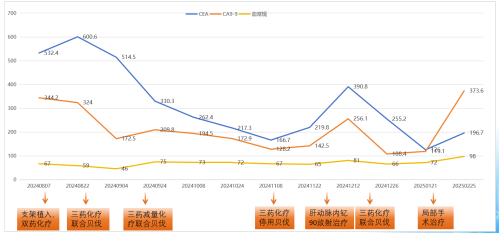

治疗4周期后,肝脏转移灶较基线缩小约20%(图5/6),CEA从532.4 ng/ml降至217.3 ng/ml,CA199从344.2 U/ml降至172.9 U/ml,评估为SD。

目前诊断:乙状结肠腺癌伴肝转移(cT3N2M1a IVA期) NRAS p.Q61L突变,TMB 6.2,MSS;中度贫血;双肺多发结节,转移待排(图7)。

肝脏病灶稍缩小(图8/9),评价为SD。但出现支架旁包裹性积气、积液,提示局部穿孔伴脓肿(图10)。

CEA、CA19-9略微升高(图17),肝脏多发转移瘤较前增多、增大(图15/16),双肺结节较前增多、增大(图14),评估为PD。

下一步治疗方案:鉴于既往三药治疗有效,手术间歇期停用全身治疗后肿标升高,则继续FOLFOXIRI联合贝伐珠单抗化疗。治疗目标为姑息性治疗1.针对该患者的后续治疗计划:是否继续FOLFOXIRI联合贝伐珠单抗化疗?是否考虑二线治疗方案(如免疫治疗、靶向治疗)?